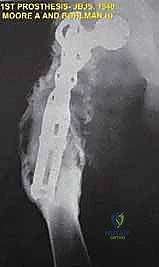

تذكروا عام 1940: نشر أوستن مور وهارولد بولمان أول عملية إعادة بناء موثقة باستخدام طرف اصطناعي داخلي – وهو عظم فخذ قريب مخصص من مادة الفيتاليوم لعلاج ورم الخلايا العملاقة. كانت هذه خطوة رائدة بالفعل. ومع ذلك، على الرغم من العمل الدؤوب لجراحي الأورام العظمية الأوائل في تحديد مستويات البتر وإدارة الجروح المعقدة، فإن هذه الاستئصالات العدوانية غالباً ما فشلت في التأثير على بقاء المريض بشكل عام، حيث ظل المرض المنتشر (Metastasis) هو السبب الرئيسي للوفاة.